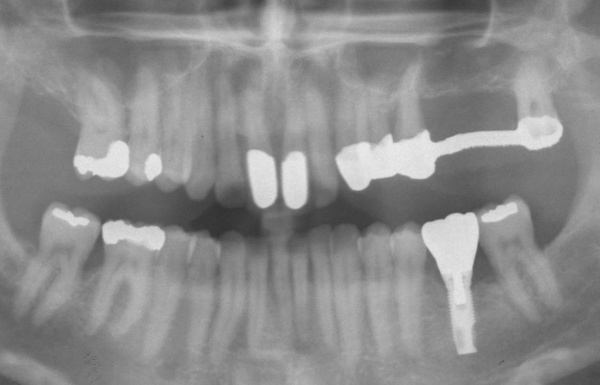

Der Erstbefund vom 20.08.1998 zeigte eine lokalisiert entzündliche marginale Gingiva mit Blutungsneigung auf Sondierung (SBI 32 %) vorrangig in regio 17, 11, 21, 24, 27, 36, 37, 41, 46. Austritt von Pus aus der Tasche an 22. Die Sondiertiefen waren durchweg erhöht, an einzelnen Parodontien konnten bis zu 12 mm sondiert werden (s. Abb. 12). Generalisiert weiche Beläge (API 46 %), harte Beläge in der UK-Front. An 41 singuläre parodontale Rezession und Zahnlockerung des Grades II, hier auch sehr schmale keratinisierte Gingiva. Mobilitätstest und Blanchingtest positiv. Der Röntgenbefund der Panoramaschichtaufnahme vom 11.08.1999 (s. Abb. 13) zeigt einen generalisierten horizontalen Knochenabbau mit vertikalen Einbrüchen in regio 17, 24, 25, 26, 36, 41 und 47. Wurzelfüllung an 36. Konkremente sichtbar. 18 elongiert. 38 und 48 halbretiniert mit Aufhellung distal.

Aufgrund der fortgeschrittenen parodontalen Destruktion mussten die Zähne 26, 27 und 36 als nicht erhaltungswürdig beurteilt werden. Zur Herstellung einer kaufunktionell und ästhetisch befriedigenden Situation wurde die Anfertigung eines festsitzenden Zahnersatzes zur Versorgung der Schaltlücke 26/27 angestrebt. Da ein definitiver Zahnersatz erst nach einer ausreichend langen Reevaluationsphase angefertigt werden sollte, wurde zunächst ein metallverstärktes laborgefertigtes Langzeitprovisoriums von 23 auf 28 im August 2000 eingegliedert (s. Abb. 14). Für die Schaltlücke 36 war zu einem späteren Zeitpunkt eine implantatprothetische Versorgung vorgesehen.

Aufgrund der fortgeschrittenen parodontalen Vorerkrankung musste mit der Planung und der Herstellung des definitiven Zahnersatzes lange gewartet werden. Zunächst wurden im Mai 2001 die erneuerungsbedürftigen Kronen der prognostisch als günstig beurteilten Zähne 11 und 21 erneuert. Im April 2002 wurde die Versorgung der Schaltlücke in regio 36 mit der Einbringung eines dentalen Implantats in regio 36 begonnen, die mit der Herstellung der implantatgetragenen Krone im November 2002 abgeschlossen wurde (s. Abb. 15). Das Langzeitprovisorium 23 auf 28 wurde im Oktober 2004 durch eine definitive Brücke von 23 auf 28 ausgetauscht.